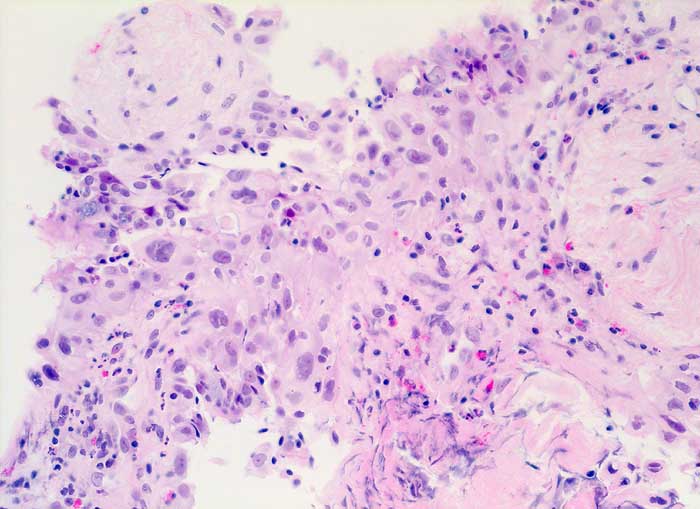

strahleninduzierte Kernatypien

Ausgeprägte Kernpolymorphie und Kernvergrösserung des respiratorischen Epithels bei erhaltener Kern-Zytoplasmarelation.